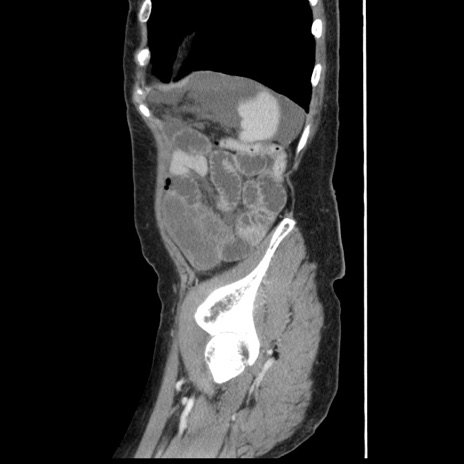

冠状断像